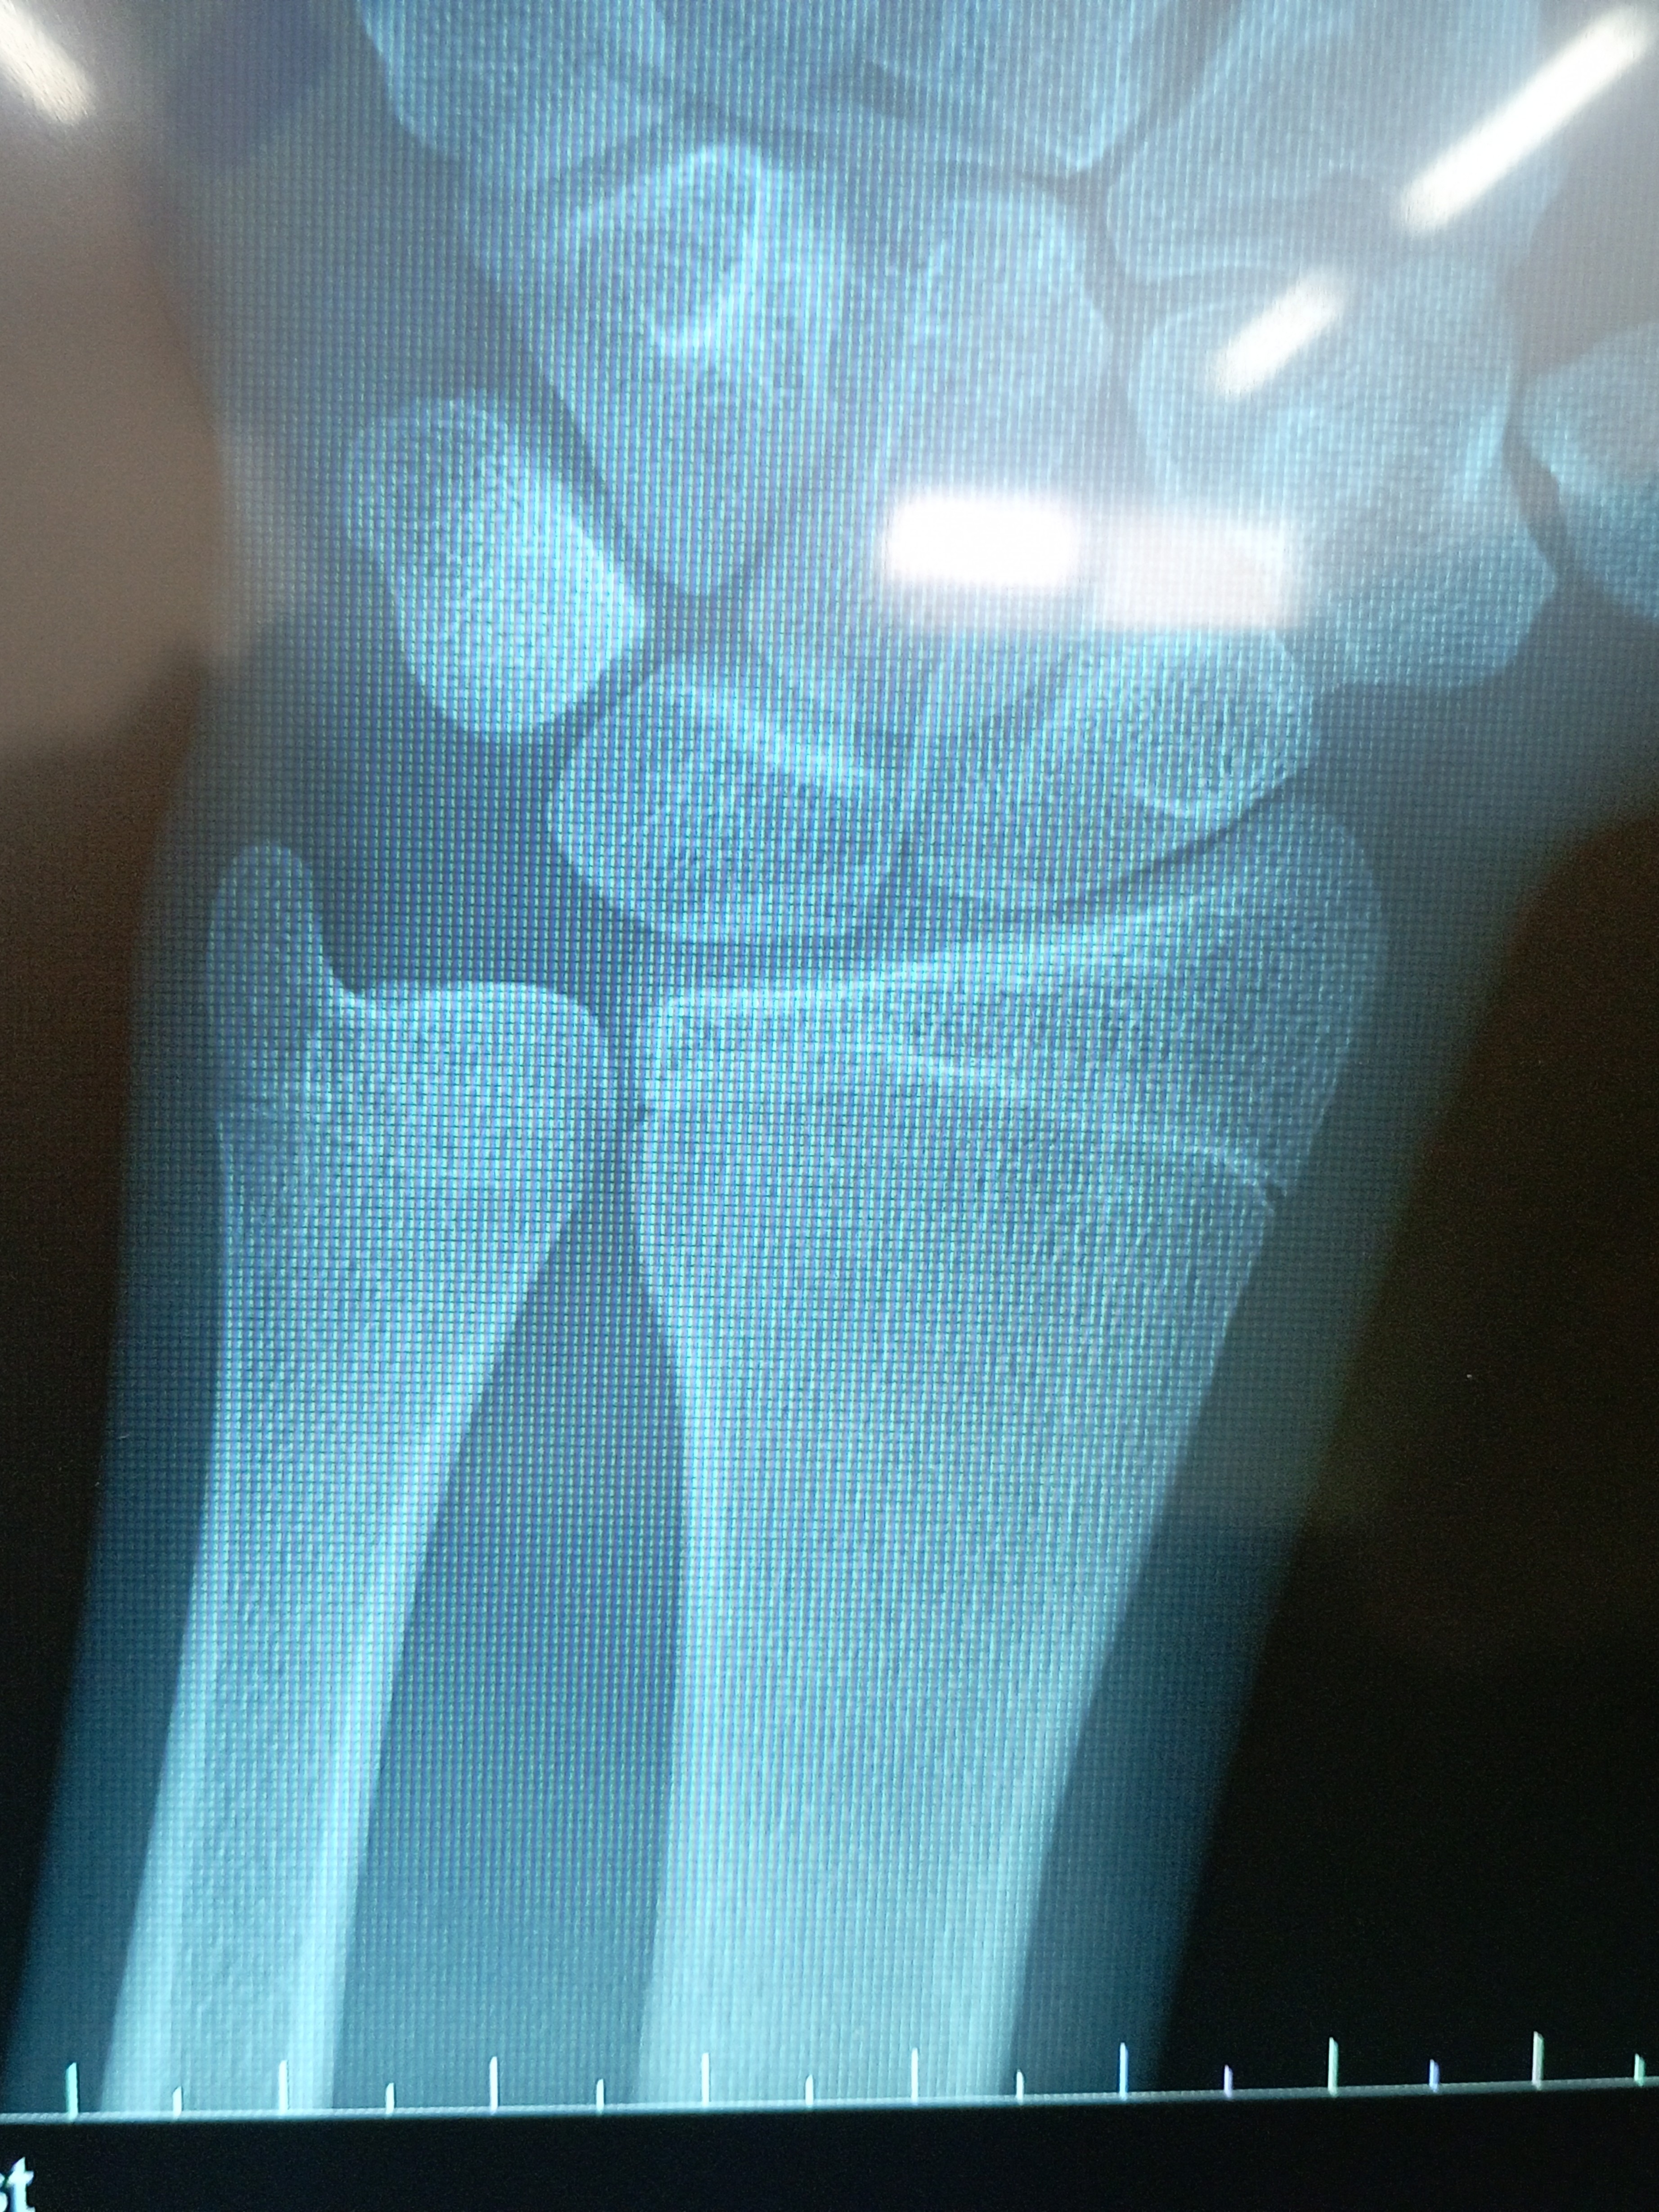

No I stopped growing ig. They said I'm done. I'm around 6'1No bruh they don’t look alike

View attachment 4852427

View attachment 4852428

Mines visibly more opened

But u got like 0.5 inches left? Wha did they tell u